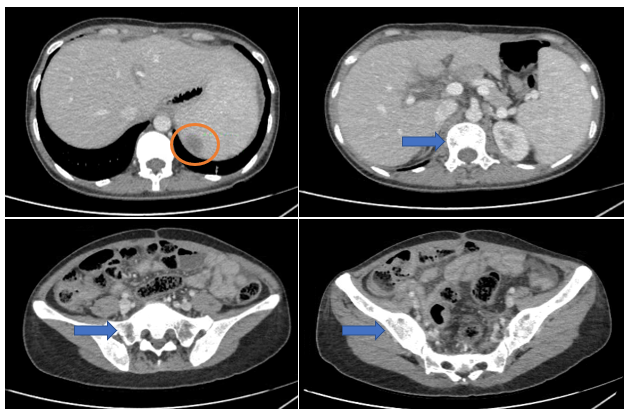

– Cắt lớp vi tính ổ bụng (30/06/2025): Cấu trúc dạng nang hỗn hợp tiểu khung nghi nguồn gốc từ buồng trứng hai bên.

Hình 5. Hình ảnh khối buồng trứng phải kích thước ~108mm (mũi tên màu cam), khối buồng trứng trái kích thước ~58mm (mũi tên màu xanh lục)trên phim chụp cắt lớp vi tính.

– Cắt lớp vi tính ổ bụng (22/10/2025): Nhu mô gan rải rác các nốt ngấm thuốc mạnh sau tiêm đường kính 6mm. Các nốt ngấm thuốc kém nhu mô lách đường kính lớn nhất 25mm. Các ổ khuyết xương lan tỏa xương cột sống và cánh chậu hai bên – theo dõi tổn thương thứ phát. Dày, tăng ngấm thuốc phúc mạc vùng tiểu khung

Hình 6. Hình ảnh nốt ngấm thuốc kém ở lách (vòng tròn màu cam). Các ổ khuyết xương lan tỏa nhiều vị trí (mũi tên màu xanh) trên phim chụp cắt lớp vi tính.